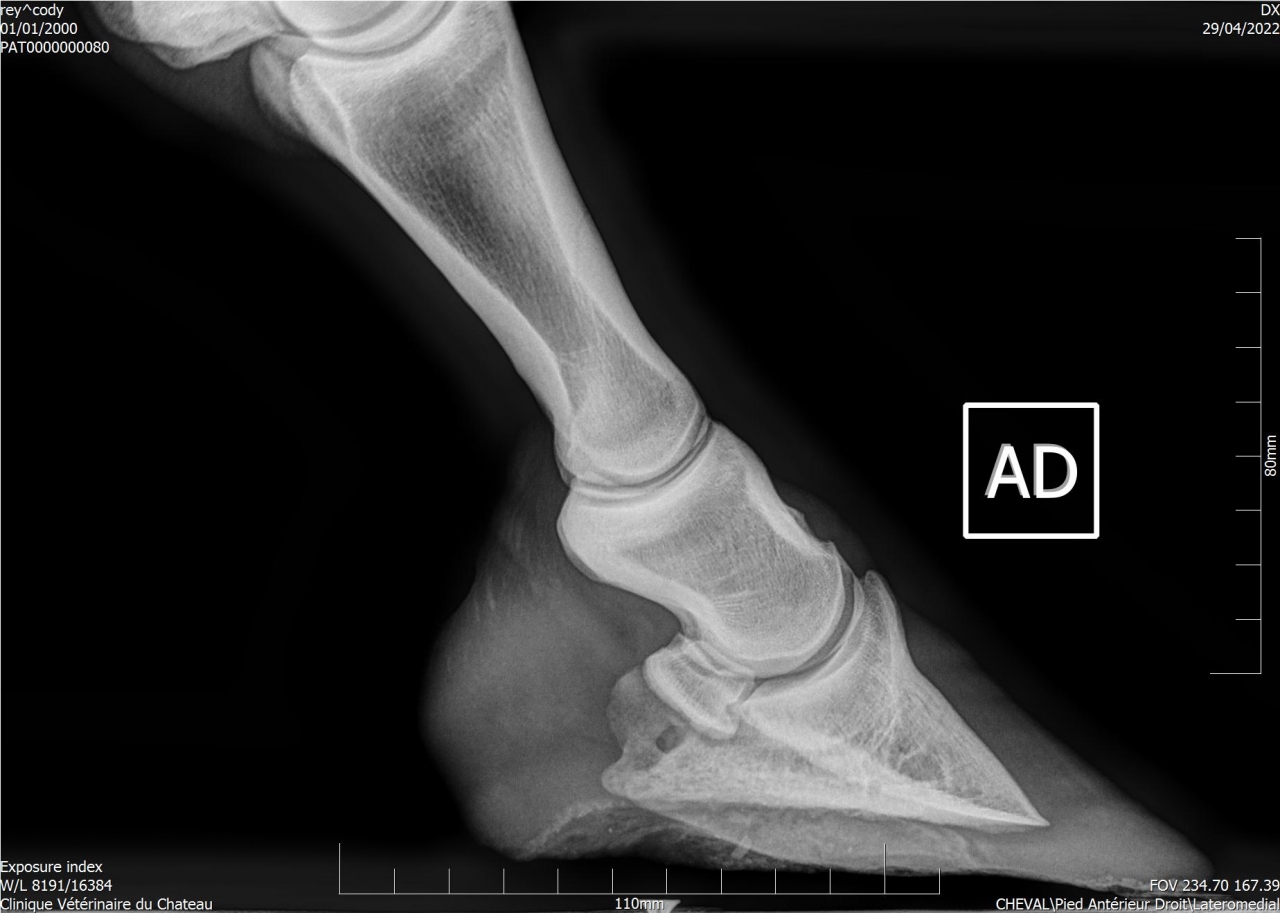

| Dire merci | Je remonte le post Mon cheval a été diagnostiqué naviculaire, il y a des fossettes synoviales. Ma véto préconise une infiltration avec du Tildren ou de l’Osphos. Aujourd'hui mon cheval a été ferré : antérieurs avec oignons et plaques en cuir, ferrure normale aux postérieurs. Voici les radios : ![]() ![]() ![]() ![]() ![]() |

| Dire merci | Les radios LM montrent une pince trop longue et pas de roll/ breakover Agir sur cela soulagera déjà énormément l’arrière du pied ! Sur la dp 60 on voit une zone noire circulaire Aurais tu une photos vue solaire stp ? Y a t’il fourmilière/évasement important voire un abcès récent ? |

| Dire merci | Je n'ai que ça comme radios ... Il y a des fourmilières aux 2 antérieurs. |